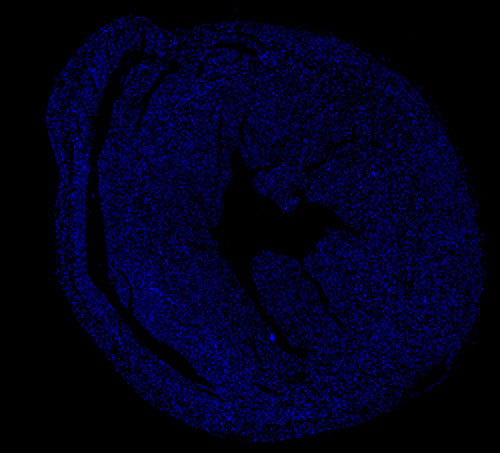

實驗結果展示:

DAPI染色-小鼠心臟